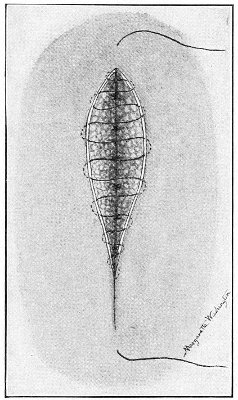

Cysts of the Vulvo-vaginal Glands.—Cysts may 41 occur in the duct of the vulvo-vaginal gland or in the gland itself. Cysts of the duct are small—about the size of a chestnut. They are situated superficially, lying immediately under the mucous membrane of the vagina at the base of the labium minus.

Fig. 18.—Cyst of the right vulvo-vaginal gland (Hirst).

Cysts of the gland may be unilocular if formed at the expense of a single lobule of the gland, or multilocular if several lobules enter into their formation. These cysts may attain the size of the fetal head (Fig. 18).

Cysts of the gland or of the duct are formed by retention of the cyst-contents. The retention is due to occlusion of the duct, usually the result of inflammation. In some cases the duct remains pervious, and the retention is due to the altered character of the secretion of the gland, which becomes too viscous to pass, except under unusual pressure, along the duct.

These cysts contain clear yellow or chocolate-colored 42 fluid. The diagnosis of cyst of the vulvo-vaginal gland is usually not difficult. If we are in doubt in regard to the fluid character of the tumor, this may be determined with the exploring-needle.

Inguinal hernia, hydrocele of the canal of Nuck, cysts of the round ligament, and sacculated cysts of old hernial sacs may be mistaken for cysts of the vulvo-vaginal glands. In such cases, however, the tumor lies more in the upper and outer part of the labium majus, and extends to, and may be connected with, the external inguinal ring.

Cysts of the vulvo-vaginal glands should be treated by free incision and packing, or by extirpation. If the sac is emptied by the aspirator or by a small incision, it will refill. The best method is to extirpate the cyst. In case there has been no inflammatory action binding the cyst to surrounding structures, extirpation without rupture is easy. If rupture occurs, the cyst-wall may be dissected off with the knife or removed with the curved scissors. The wound may be immediately closed with deep and superficial sutures.